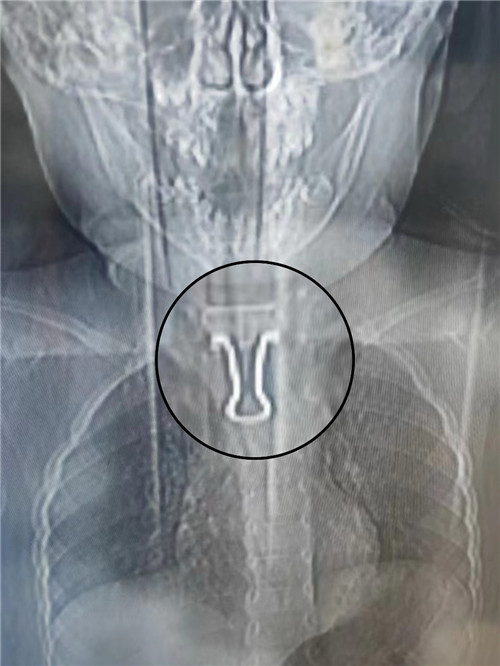

CT檢查結果顯示,燕尾夾金屬面朝上,尾柄接近心臟主動脈弓,卡在食管里。金屬夾邊角尖銳,易劃傷食管,且幼兒食管入口比成人窄,很難取出。在綜合評估病情后,耳鼻咽喉頭頸外科團隊決定迎難而上,立即施行食管鏡食管異物取出術。

“異物位置太刁鉆了!”為了不傷到幼兒食管“一絲一毫”,科室團隊全程半蹲手術,小心翼翼反復嘗試了多種工具,終于成功將異物取出,幼兒轉危為安,現(xiàn)已出院。